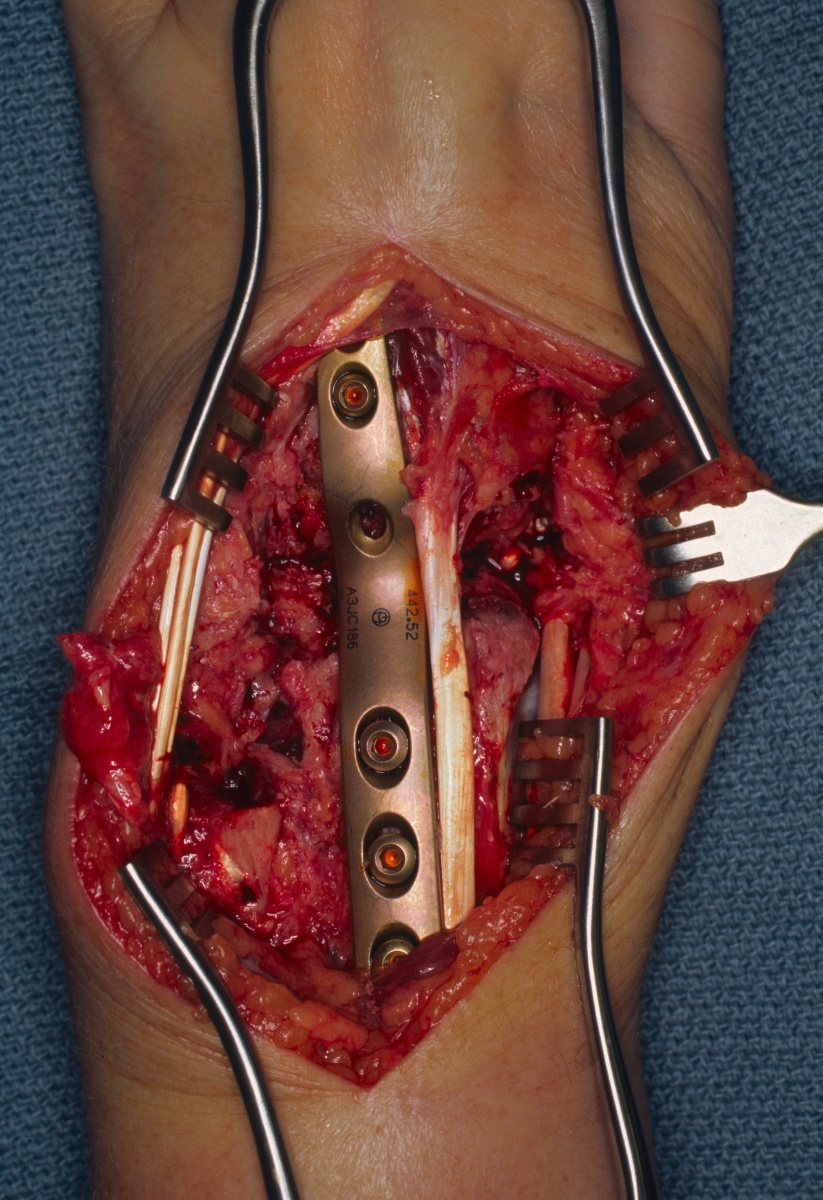

| Eventually, she was treated with wrist fusion, distal ulnar resection and extensor carpi ulnaris tenodesis, and basal joint excision arthroplasty with split abductor pollicis longus anchovie interposition and ligament reconstruction - all through a single dorsal approach.: |